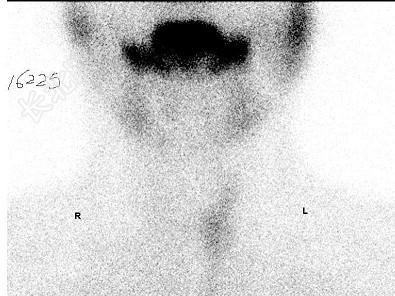

- 单项选择题32岁男性,无明显诱因发现右颈部包块, 感疼痛1个月,行99TcmO4-甲状腺静态显像如图, 最可能诊断为 ( )

E、右甲状腺腺瘤